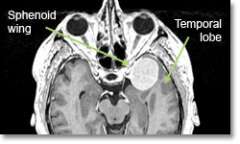

Meningioma Sphen

Location - Sphenoid Ridge

Common Symptoms

- Eye-bulging, decreased vision, paralysis of eye movement, seizures, memory difficulty, personality change, headache.